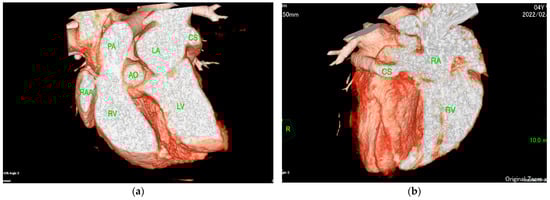

The ECG-gated CT showed communication between the LA and RA via the CS (Figure 2a). An enlargement of the CS, where the coronary artery measured 0.8 mm in diameter, whereas the CS measured 11.6 mm, was observed (Figure 2b). The CS drained normally into the RA; however, an ostium to the LA was seen, leading to the diagnosis of UCSS (Figure 3a). Under general anesthesia, TEE was also conducted using LISSENDO 880LE (Fujifilm Ltd., Tokyo, Japan) equipped with the 8–2 MHz phase array transesophageal probe (Fujifilm Ltd., Tokyo, Japan). With TEE, it was possible to identify the shunt as an abnormally large CS running along the cardiac wall (Figure 4).

Figure 3. (a) ECG-gated CT volume rendering (sagittal slice, right lateral view, observed from the left) showing the CS connecting to the LA. (b) ECG-gated CT volume rendering (oblique sagittal slice, right lateral view, observed from the right) showing the CS connecting to the RA. CS, coronary sinus; RA, right artery; RV, right ventricle; LA, left atrium; LV, left ventricle; AO, aorta; PA, pulmonary artery; RAA, right atrial appendage.